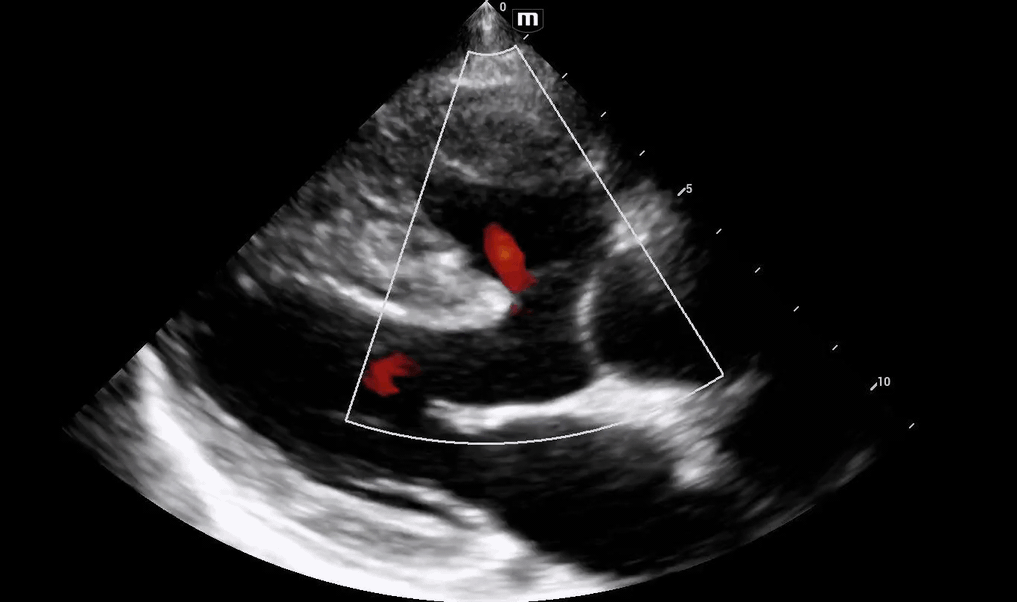

Initial POCUS shows abnormality in the ventricular septal wall (PSL 1 above), and upon putting color doppler, imaging was highly suspicious for a VSD.

The patient's aortic outflow tract also appeared to be enlarged and received flow from both the LV and RV, concerning for an “overriding aorta” (PSL 2 above).